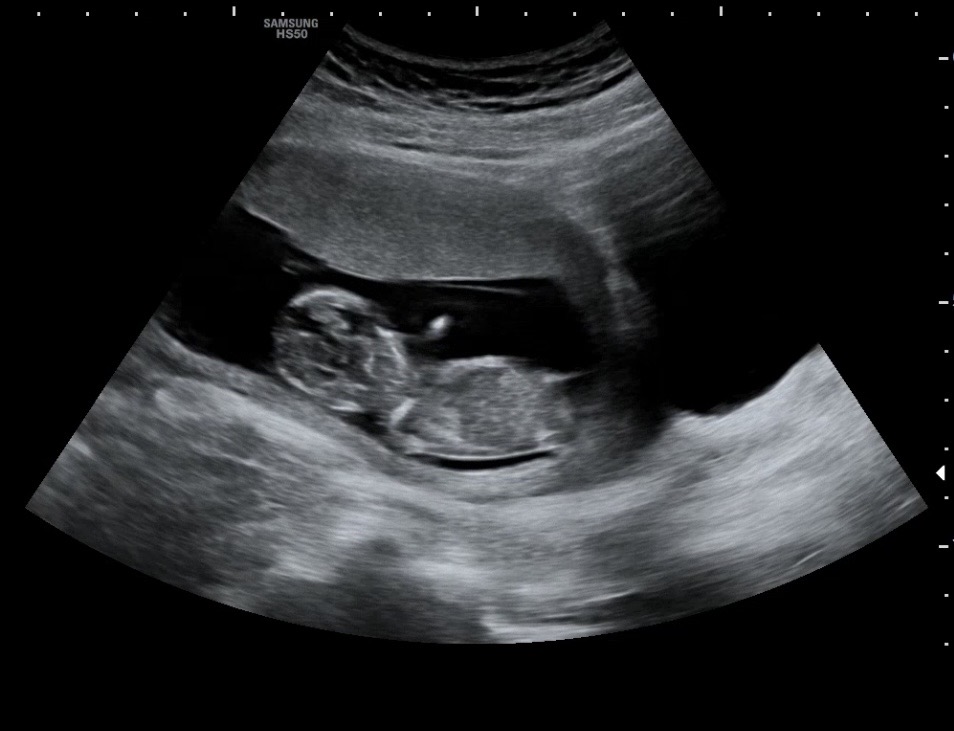

12주 5일 각도법 봐주세요!

딸일까요 아들일까요?